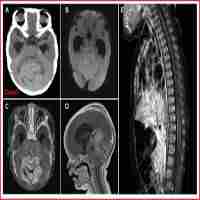

| Abstract | Gorlin-Goltz syndrome, also known as nevoid basal cell carcinoma syndrome, is caused by genetic alteration produced by a mutation in the 'patched' tumour suppressor gene, and is inherited in a dominant autosomal way. Although sporadic cases have been found, this syndrome has rarely been reported in twin patients. The syndrome is characterised by a wide range of developmental abnormalities and has a predisposition to neoplasms such as multiple pigmented basal cell carcinomas and keratocysts in jaws; it also has other features such as palmar and/or plantar pits and calcification of falx cerebri. Owing to the critical oral and maxillofacial manifestations of this syndrome, it is important to recognise its characteristics in order to make a diagnosis, and to plot early preventive treatment and establish the right genetic evidence. Based on a combination of imaging, clinical and histopathological findings, we present a diagnosed case of Gorlin-Goltz syndrome in 18-year-old twin brothers. All cystic lesions were enucleated and 1â year follow-up showed no recurrence. |